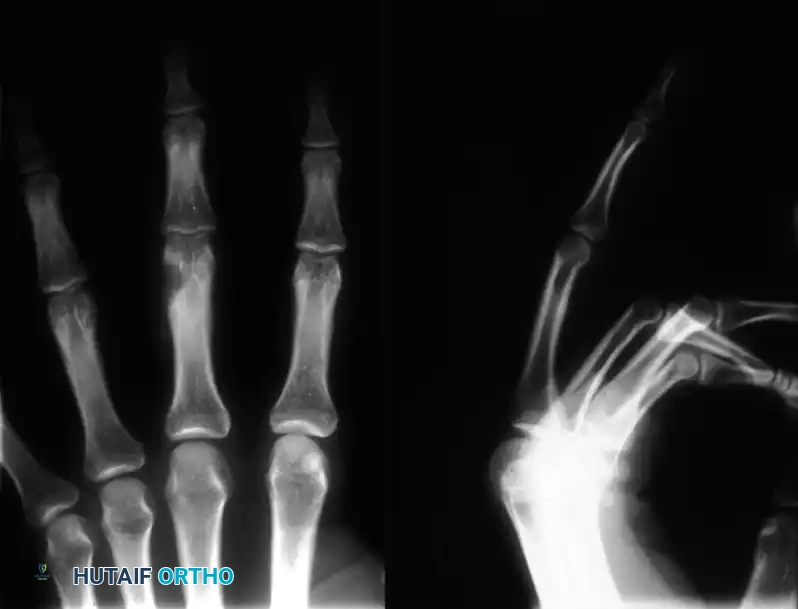

Giant cell tumors of the tendon sheath (GCTTS) are the second most common solid cellular tumors of the hand. They occur most frequently between the ages of 8 and 80 years and exhibit a strong predilection for the palmar aspect of the digits. Multiple xanthomas may be indicative of underlying hypercholesterolemia.

Clinical and Histological Profile

GCTTS are typically slow-growing, painless masses. However, when located adjacent to a joint (most commonly the proximal interphalangeal joint), they can mechanically block flexion or extension. Grossly, they appear as yellow or tan lobulated masses. Histologically, they are composed of spindle cells, fibrous tissue, cholesterol-laden histiocytes, multinucleated giant cells, and hemosiderin deposits.

Surgical Excision and Recurrence

Excision is notoriously difficult. These tumors frequently wind in and around the flexor tendons, their synovial sheaths, digital nerves, and occasionally the extensor mechanism, sometimes encompassing three-fourths of